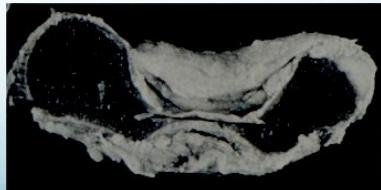

Fat Pad Sign:

- Posterior fat pad always appears in bleeding/hemoarthrosis - always abnormal

- Anterior fat pad may appear in bleeding

Important: If there’s no fracture line but there’s fat pad, treat it as minimally displaced with back slab for 2-3 days and repeat X-ray